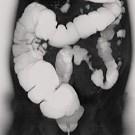

问题 女,56岁,腹胀、腹痛、左下腹包块三月余,无肛门排气,影像检查如图,最可能的诊断是 ( )

选项 A.乙状结肠Crohn病 B.乙状结肠结核 C.乙状结肠腺癌 D.乙状结肠淋巴瘤 E.乙状结肠息肉

答案 C